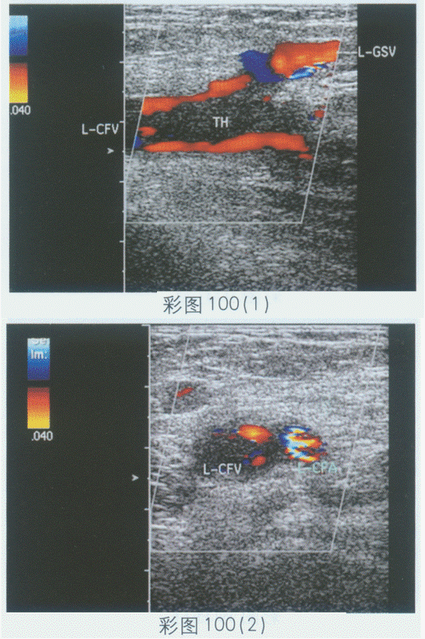

169、单项选择题

临床资料:女,24岁,自述左下肢持续性疼痛1周,加重伴肿胀2天。临床物理检查:左下肢肿胀。超声综合描述:左股总静脉内透声不清亮,可见低回声,探头加压后管腔不消失,CDFI:低回声区内未见血流信号,其旁可见条样血流信号。见彩图100。

超声提示()。

A.左股总动静脉瘘

B.左股总静脉先天畸形

C.左股总动脉栓塞

D.左股总静脉血栓